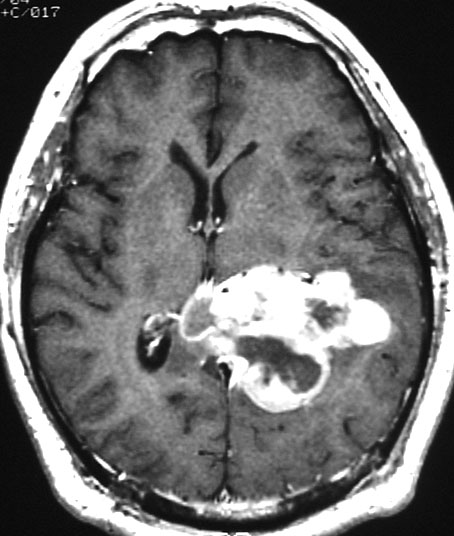

画像と病理所見4

40代男性の大脳鎌テント接合部の硬膜に発生したグレード3です。激しい出血のために腫瘍摘出を部分摘出で中断せざるを得なかった例です。

この例でも,硬膜発生腫瘍ということは手術前の画像診断で解ってはいたのですが,髄膜腫と異なり不整な形をしてのう胞があり,一部は腫瘍壊死でした。